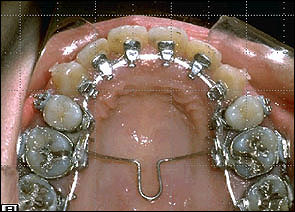

STEP 3. Anterior torque control

TMA 0175*0175